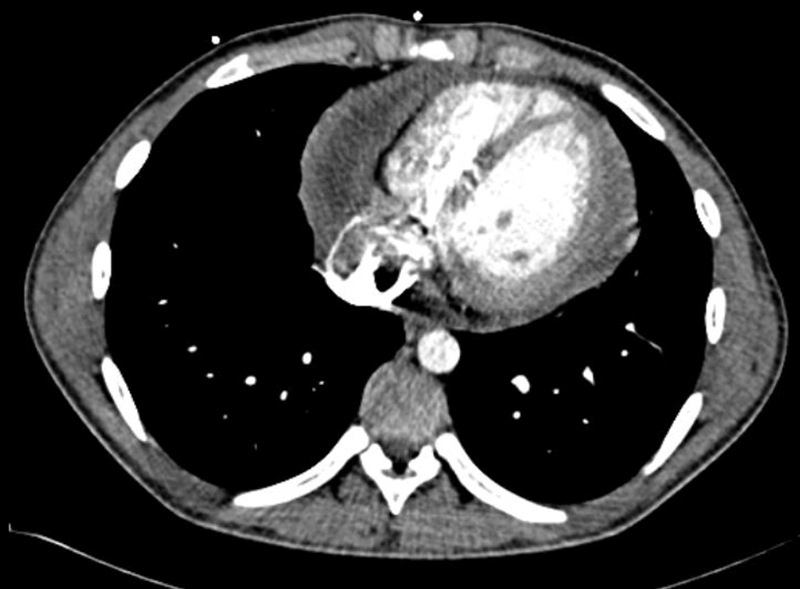

Figure 3: CT thorax showing a large pericardial effusion

Figure 3: CT thorax showing a large pericardial effusion(click to enlarge)

An urgent cardiac CT and cardiac MRI were arranged, both of which confirmed the initial findings and revealed additional evidence of tethering pericardial constriction and even some pericardial calcification. His Mantoux test was reactive 14mm but he had prior exposure to BCG.